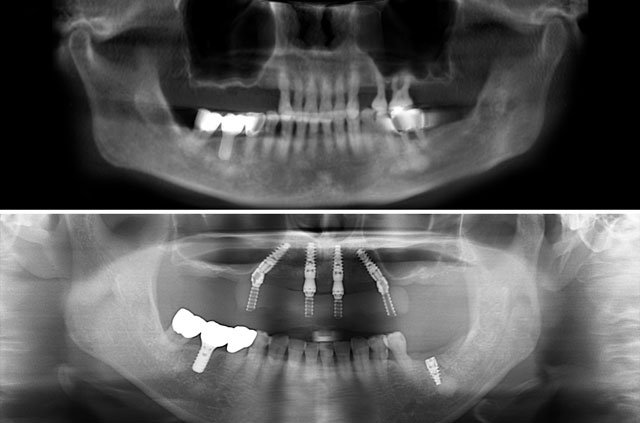

All-on-4 and immediate implant solutions for complete smile restoration. These cases showcase our expertise in full-arch rehabilitation with same-day teeth, providing patients with immediate functional and aesthetic results.

No Bone Grafting

Strategic implant placement often eliminates the need for bone grafting procedures

All-on-4 is a revolutionary dental implant technique that uses just four strategically placed implants to support a full arch of replacement teeth. The posterior implants are angled at 30-45 degrees to maximize bone contact and avoid anatomical structures like the maxillary sinus or inferior alveolar nerve. This innovative approach allows for immediate loading with a temporary prosthesis, providing same-day teeth and eliminating the need for lengthy healing periods between procedures.